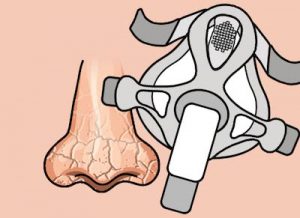

鼻子(zǐ)幹燥和(hé)喉嚨痛

連接到(dào)CPAP裝置上(shàng)的(de)加濕器(qì)通(tōng)過向空(kōng)氣提供涼爽或加熱(rè)的(de)濕氣來(lái)減少(shǎo)鼻子(zǐ)幹燥和(hé)喉嚨痛。

鼻塞,流鼻涕和(hé)打噴嚏

使用(yòng)生(shēng)理(lǐ)鹽水(shuǐ)鼻噴霧劑可(kě)以緩解輕度的(de)鼻充血。服用(yòng)非處方的(de)鼻充血劑是(shì)另一(yī)種•選擇。在嚴重的(de)情況下(xià),您的(de)醫(yī)生(shēng)可(kě)能(néng)會(huì)給您開(kāi)一(yī)個(gè)更強的(de)充血藥。